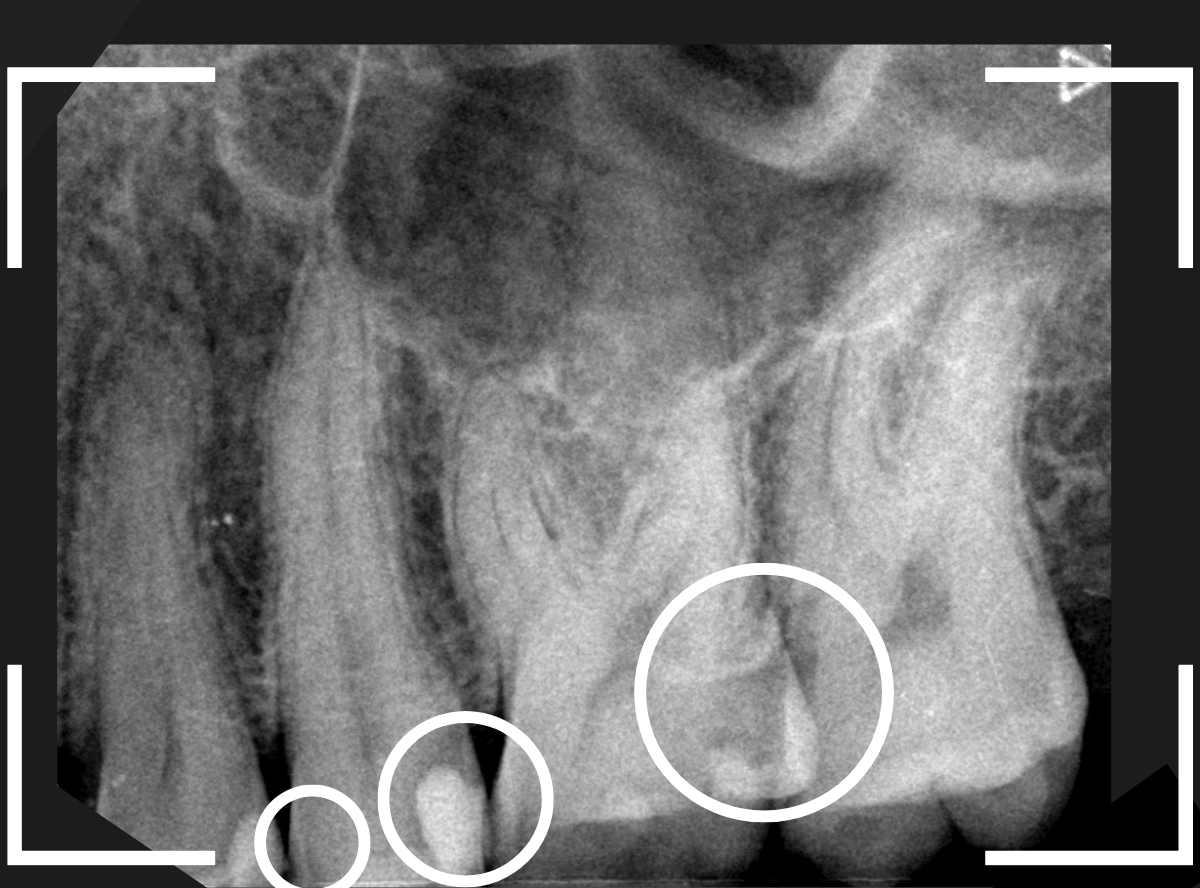

Case.25 深い虫歯の治療~無事にセラミック・インレーへ

今回は、上の奥歯が深くて広い虫歯になっていた方のケースです。

〇部が虫歯の部分です。

この写真からは深い虫歯があるのは想像つきません。

レントゲン写真で確認します。

青い線が神経、赤い線が虫歯の部分です。

前後の歯とも、かなり深く広い虫歯になっているのがわかります。